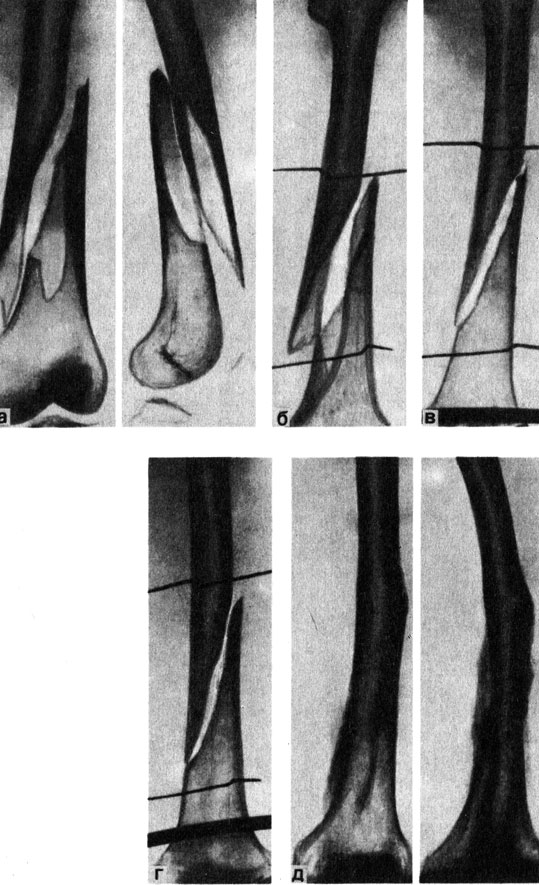

Классификация переломов диафиза бедренной кости: Иллюстрации и информация